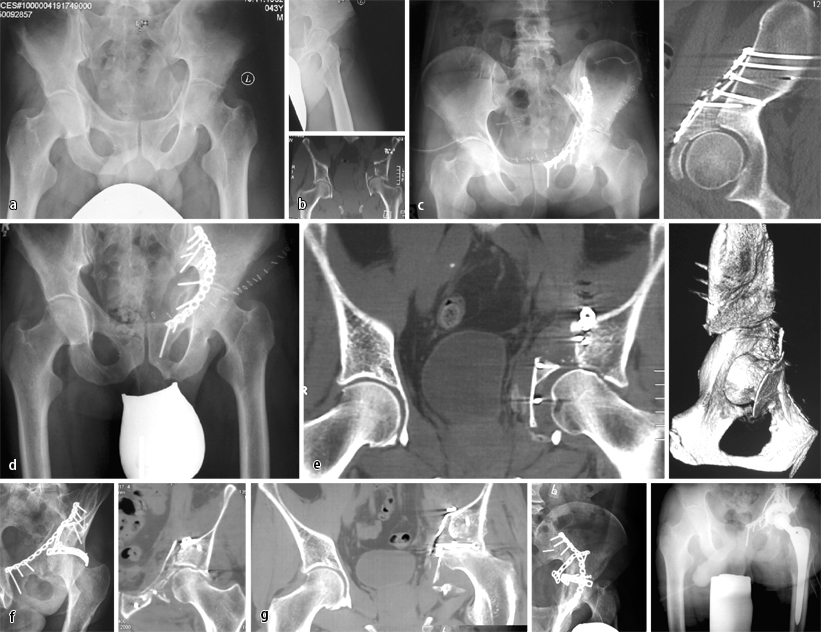

Neben der klinischen Untersuchung ist die konventionelle Röntgenbilddiagnostik die Standardbildgebung (Ausgangsbild) und bleibt dies vorläufig auch. Auch in der Zeit der vielzeiligen Spiral-CT mit multiplanarer Rekonstruktion erscheint das a.-p. Röntgenbild des Beckens bis auf weiteres unverzichtbar zur Erstbeurteilung [13]. Insbesondere, wenn eine umgehende Indikation zur CT gestellt wird, wird die nahe Zukunft zeigen, inwieweit die typischen Standardserien (a.-p. plus Ala- und Obturatoraufnahme bei der Azetabulumfraktur, a.-p. plus Inlet- und Outlet-Aufnahme bei Beckenringverletzungen; Fall 1, Abb. 1, Fall 2, Abb. 2) durch die entsprechenden CT-Rekonstruktionen ersetzt werden können (Fall 2, Abb. 2). Volumenorientierte 3D-Rekonstruktionen bieten eindrückliches Bildmaterial, können bei geringer Dislokation der Frakturen aber die Frakturerkennung erschweren [22]; zur Bewertung der eigentlichen Pfannenregion ist bei Azetabulumfrakturen das „Herausrechnen“ des Femurkopfs nötig.

Die Standardbilddiagnostik bildet derzeit noch die Grundlage der Frakturklassifikation [13]. Wird das primäre Standardröntgenbild, das etwa zum Frakturausschluss angefertigt wird, fehlinterpretiert, resultiert oft auch eine therapeutische Fehlentscheidung (Fall 1, Abb. 1).

Fall 1, 32-jährige Patientin, AO-Fraktur 61B2.1., a a.-p. Beckenübersichtsaufnahme, b CT: Kompressionsfraktur der rechtsseitigen Massa lateralis, c a.-p. Beckenübersichtsaufnahme postoperativ, d,e Beckenübersichts- und Inlet-Aufnahme nach Entfernung des Fixateurs und Vollmobilisation, weitere Erläuterungen s. Kasuistik

Fall 2, 21-Jähriger mit isolierter bilateraler transforaminaler Sakrumfraktur AO 61C3.3), a Outlet- und Inlet-Aufnahme, b 3D-Oberflächenrekonstruktion in analoger Projektion, c CT-Nativschnitt und sagittale 2D-Rekonstruktion, d volumenorientierte Rekonstruktion, e a.-p., Inlet- und Outlet-Aufnahme nach Versorgung mit triangulärer bilateraler spinopelviner Transfixation, weitere Erläuterungen s. Kasuistik

Fall 3, 24-Jähriger mit isolierter Beckenringverletzung AO 62C1.3, a unzureichende a.-p. Aufnahme des Beckens, b CT mit koronarer Rekonstruktion: C-Verletzung mit vertikalem Versatz, Abriss des Querfortsatzes von LWK5 rechts, mehrfragmentärer Stauchungsfraktur des Sakrums, c offene Reposition, weitere Erläuterungen s. Kasuistik

Fall 6, 43-jähriger Patient, a,b AO-Verletzung 62B3.2 mit erheblicher Trümmerzone der vorderen Azetabulumwand, des vorderen Pfeilers, der quadrilateralen Fläche, c inkomplette Reposition (intraartikuläre Stufe, Pfanneninkongruenz), d,e weitere Dislokation unter Mobilisation, f residuale Inkongruenz der Hüftpfanne nach Revision, g Teilimplantatentfernung und Hüft-TEP, weitere Erläuterungen s. Kasuistik

Fall 7, 52-jähriger Polytraumapatient (AO 62A2.3), a,b erhebliche Impressionszonen und osteochondrale Frakturen im Pfannendachbereich, c intraoperative Kontrolle von Reposition und Implantatlage nach ORIF mit 3D-Bildverstärker, d Entfernung der markierten Zugschraube und nochmalige 3D-Bildverstärker-Kontrolle, e,f postoperatives a.-p. Röntgenbild und 2D-Rekonstruktion nach CT, weitere Erläuterungen s. Kasuistik

Die 32-jährige Patientin war im europäischen Ausland gestürzt und nach Vorlage der a.-p. Beckenübersichtsaufnahme (Abb. 1 a) mit „stabiler“ isolierter vorderer Beckenringfraktur unter starken Beschwerden voll mobilisiert worden. Die rechtsseitige Sakrumfraktur wurde erst 10 Tage nach dem Trauma und der Rückkehr in die Heimat diagnostiziert (Abb. 1 b).

Die Fraktur wurde reponiert und mittels supraazetabulärem Fixateur externe und transiliosakraler Stellschraube stabilisiert (Abb. 1 c). In Abb. 1 d,e sind die Beckenübersichts- und Inlet-Aufnahme nach Entfernung des Fixateurs und Vollmobilisation dargestellt.

Fall 2

Bei dem 21 Jahre alten Mann lag eine isolierte bilaterale transforaminale Sakrumfraktur AO 61C3.3 („blow-out-fracture“) vor. Die Diagnose erfolgte mittels Outlet- und Inlet-Aufnahme, 3D-Oberflächenrekonstruktion in analoger Projektion, CT-Nativschnitt und sagittaler 2D-Rekonstruktion sowie volumenorientierter Rekonstruktion (Abb. 2 a–d).

Nach Reposition wurde die Verletzung mit triangulärer bilateraler spinopelviner Transfixation versorgt (Abb. 2 e).

Fall 3

Bei dem 24 Jahre alten männlichen Patienten war es bei einem Motorradunfall zu einer isolierten Beckenringverletzung (AO 62C1.3) gekommen. Die a.-p. Aufnahme des Beckens (Abb. 3 a) war lagerungs- und aufnahmetechnisch unzureichend. Die CT-Aufnahmen mit koronarer Rekonstruktion belegten eine C-Verletzung mit vertikalem Versatz sowie Abriss des Querfortsatzes von LWK5 rechts und eine mehrfragmentärer Stauchungsfraktur des Sakrums (Abb. 3 b).

Die Versorgung erfolgte durch offene Reposition der Sakrumfraktur mit winkelstabiler Platte und spinopelviner Transfixation bzw. supraazetabulärem Fixateur externe.

Fall 6

Bei dem 43-jährigen Mann (AO 62B3.2) bestand eine erhebliche Trümmerzone der vorderen Azetabulumwand, des vorderen Pfeilers sowie der quadrilateralen Fläche.

Aufgrund des inkompletten Repositionsergebnisses mit intraartikulärer Stufe und Inkongruenz der Pfanne kam es unter Mobilisation zu einer weiteren Dislokation. Nach der Revisionsoperation über einen doppelten Zugang (ilioinguinal und Kocher-Langenbeck-Zugang) lag dennoch eine residuale Inkongruenz der Hüftpfanne vor.

Im weiteren Verlauf entwickelte sich binnen 6 Monaten eine Femurkopfnekrose mit konsekutiver Indikation zur Teilimplantatentfernung und Hüft-TEP (Abb. 7).

Fall 7

Der 52-jährige männliche Polytraumapatient (AO 62A2.3) wies erhebliche Impressionszonen und osteochondrale Frakturen im Pfannendachbereich auf.

Nach ORIF über einen erweiterten dorsalen Zugang mit Trochanter-Flip-Osteotomie wurden die Reposition und die Implantatlage intraoperativ mit dem 3D-Bildverstärker kontrolliert. Die dabei identifizierte „Schwachstelle“ der operativen Versorgung wurde in gleicher Sitzung behoben und das Ergebnis erneut intraoperativ kontrolliert.

Die postoperative Röntgenuntersuchung und CT-Rekonstruktion bestätigten den Befund der intraoperativen Kontrollaufnahme (Abb. 8).